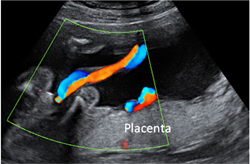

- Cribado de preeclampsia (hipertensión arterial en la segunda mitad del embarazo). La medición del índice de pulsatilidad en las arterias uterinas (por ecografía Doppler pulsado) puede ayudar en la detección de embarazadas con riesgo desarrollar preeclampsia durante el embarazo.